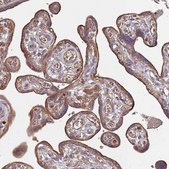

immunohistochemistry: 1:50-1:200

The Human Protein Atlas project can be subdivided into three efforts: Human Tissue Atlas, Cancer Atlas, and Human Cell Atlas. The antibodies that have been generated in support of the Tissue and Cancer Atlas projects have been tested by immunohistochemistry against hundreds of normal and disease tissues and through the recent efforts of the Human Cell Atlas project, many have been characterized by immunofluorescence to map the human proteome not only at the tissue level but now at the subcellular level. These images and the collection of this vast data set can be viewed on the Human Protein Atlas (HPA) site by clicking on the Image Gallery link. We also provide Prestige Antibodies® protocols and other useful information.

- IHC tissue array of 44 normal human tissues and 20 of the most common cancer type tissues.